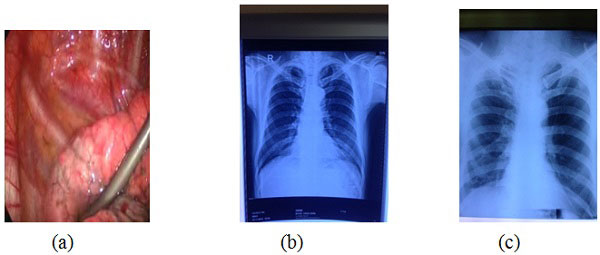

Hình ảnh phẫu phuật nội soi cắt giảm thể tích phổi (a), Xquang phổi trước phẫu thuật (b) và sau phẫu thuật 1 tháng (c) của bệnh nhân. |

Hàng năm, bệnh nhân phải nằm bệnh viện nhiều lần vì đợt cấp của bệnh. Trên hình ảnh chụp cắt lớp vi tính lồng ngực thấy khí thũng ở cả 2 phổi và nặng nhất ở thùy dưới phổi phải. Đo chức năng hô hấp có rối loạn thông khí nặng: FEV1 23,4% số lý thuyết (SLT), thể tích cặn tăng (193% SLT), dung tích toàn phổi tăng (126% SLT). Bệnh nhân đã được điều trị và chuẩn bị trước phẫu thuật tại Khoa lao và bệnh phổi. Ngày 20/11/2014, dưới sự chỉ đạo của GS.TS. Đồng Khắc Hưng - Phó Giám đốc HVQY, PGS.TS. Hoàng Mạnh An - Giám đốc BV Quân y 103, kíp phẫu thuật đã tiến hành cắt bán phần thùy giữa và dưới phổi phải qua nội soi cho bệnh nhân. Sau 1 tuần điều trị hậu phẫu, sức khỏe bệnh nhân ổn định và ra viện. Kiểm tra lại 1 tháng sau phẫu thuật, tình trạng sức khỏe bệnh nhân được cải thiện rõ rệt: khó thở giảm nhiều, bệnh nhân đi lại thấy dễ dàng, thoải mái hơn; đo chức năng hô hấp có cải thiện rõ rệt (FEV1 tăng lên 53% SLT), bệnh nhân tăng cân so với trước phẫu thuật. Bệnh nhân được tiếp tục kiểm tra và tư vấn điều trị định kì tiếp theo hàng tháng.